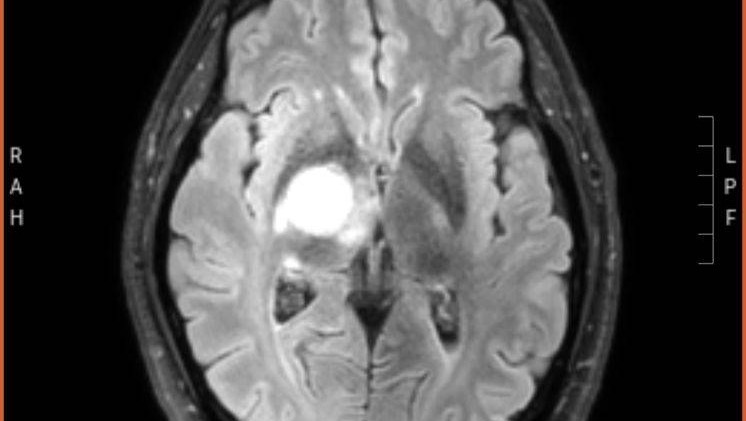

Sadly it has grown a lot. But doctors haven’t spoke with him yet, he got this today from his portal online. Please pray!!

Here is a picture of the tumor, the egg shaped spot is it.